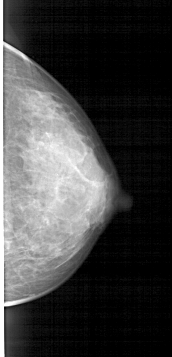

A_1446_1.LEFT_CC

LEFT_CC LINES 4711 PIXELS_PER_LINE 2296 BITS_PER_PIXEL 12 RESOLUTION 43.5 OVERLAY